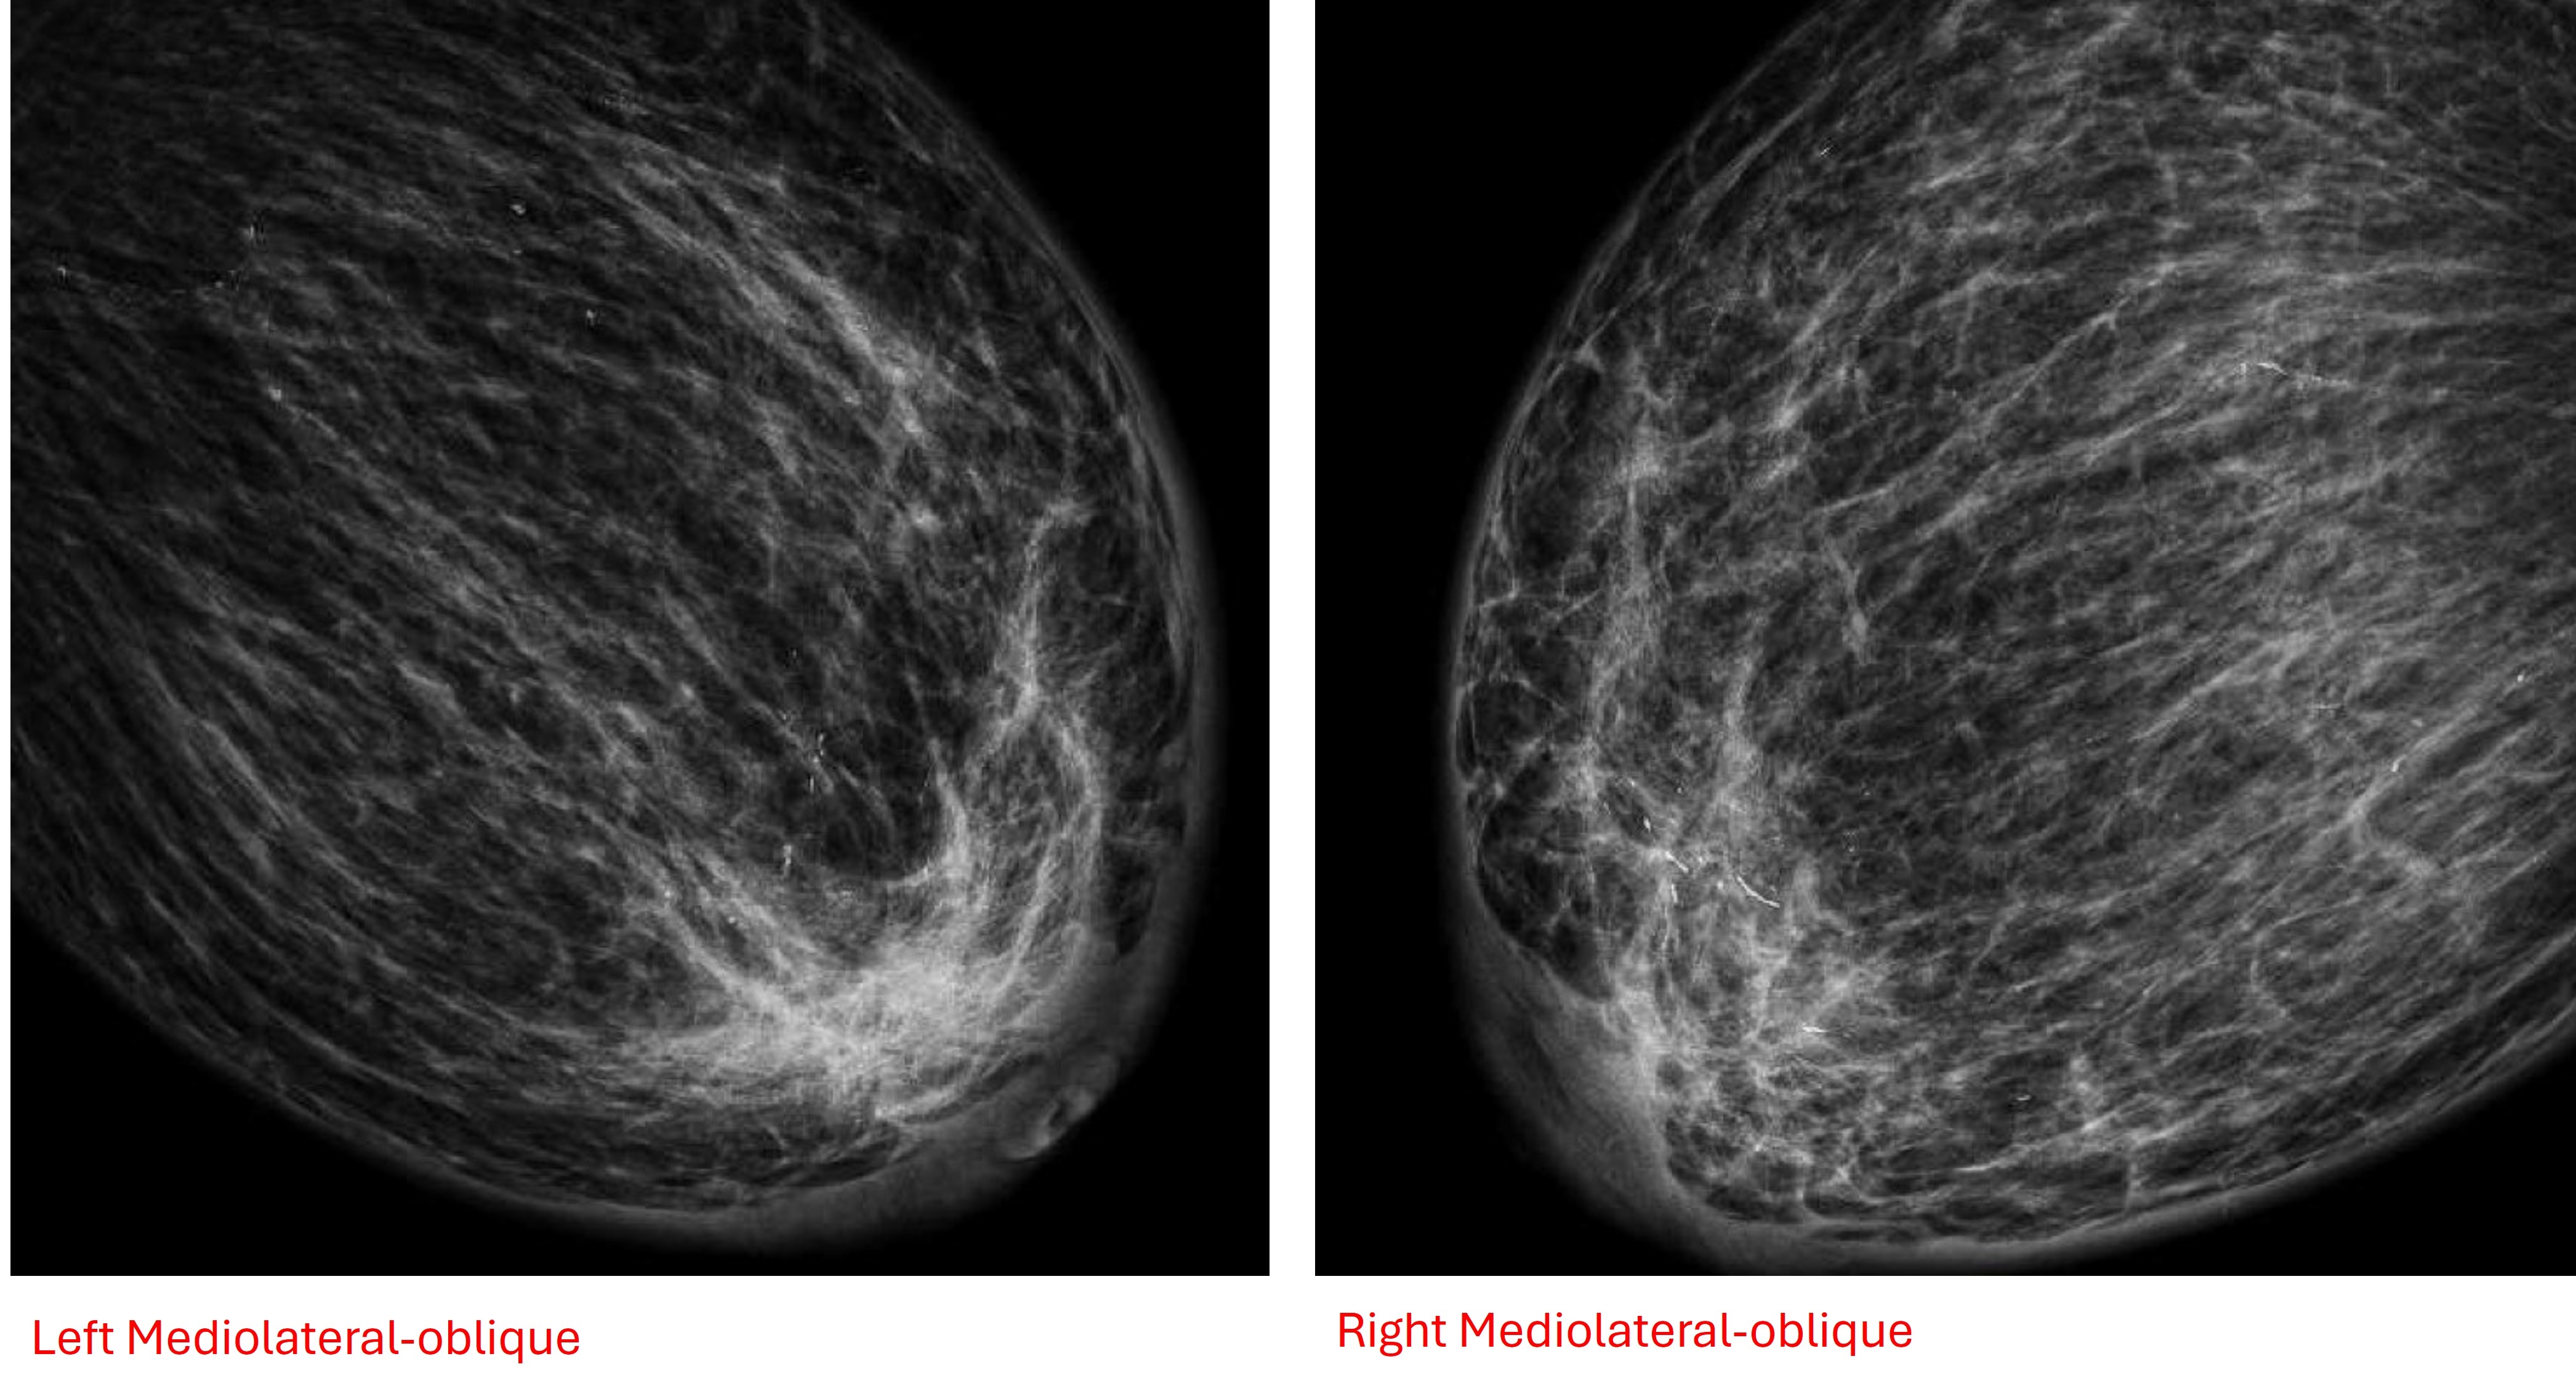

Case Presentation: A 77-year-old female presented with acute onset bilateral breast enlargement, tenderness, and erythema, along with symptoms of CHF exacerbation including dyspnea, orthopnea, and lower extremity edema. Physical examination revealed markedly enlarged, tender breasts. Imaging studies including mammography (Figure 1: Right and left craniocaudal views; Figure 2: Right and left mediolateral oblique views) and breast ultrasound showed diffuse skin and subcutaneous edema without evidence of infection or malignancy. Echocardiography confirmed reduced ejection fraction and diastolic dysfunction. Skin biopsy findings were consistent with CHF-related changes. The patient's symptoms improved with diuresis and optimization of guideline-directed medical therapy for heart failure.